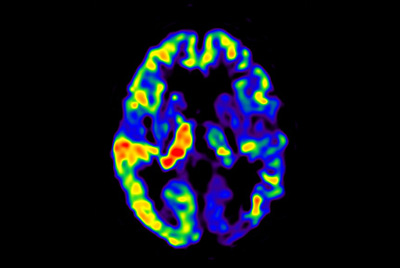

Alzheimer’s Disease Anti-Amyloid Immunotherapies (ARIA) 3.0T

Alzheimer’s Disease Anti-Amyloid Immunotherapies (ARIA) 1.5T

NeuroQuant

Contrast-free brain perfusion

Advanced Neuro imaging - pCASL